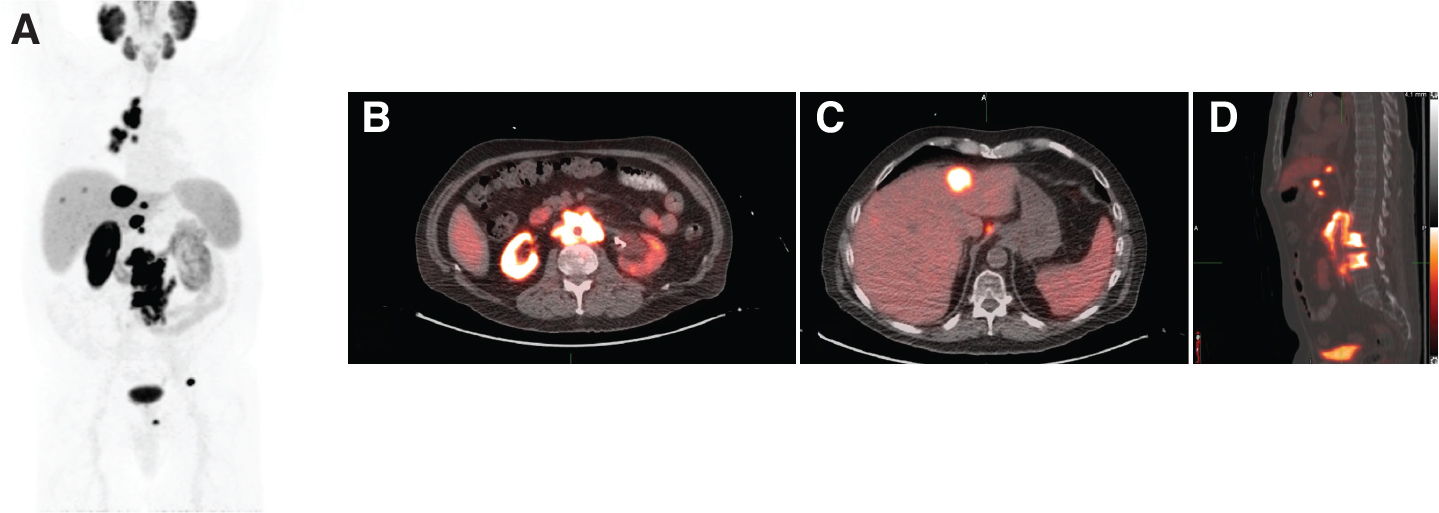

Recently, two PSMA-targeting molecular imaging agents Gallium-68 prostate specific membrane antigen (68Ga-PSMA-11) and fluorine-18 piflufolastat (18F-DCFPYL) received FDA approval after the completion of two landmark clinical trials, VISION and TheraP, which evaluated their safety and efficacy in treating metastatic castrate-resistant prostate cancer. These two agents have superior sensitivity and specificity profiles for recurrent or metastatic prostate cancer than the earlier approved PET molecular imaging agents (i.e., 18F-fluciclovine [Axumin] and 11C-choline). PSMA-targeting diagnostic imaging is critical in identifying eligible patients who can benefit from 177Lu-PSMA therapy (Figure 1) and serves as a diagnostic component in 177Lu- PSMA theranostics. At present, there is no definitive consensus on what amount of PSMA uptake in a metastatic lesion is considered sufficient for a patient to derive significant benefit from 177Lu-PSMA therapy. Following the example of neuroendocrine tumor theranostics, adequate uptake is generally considered when most metastatic lesions show uptake higher than that of normal organs such as the liver. For example, the inclusion criteria of the TheraP phase 2 trial of 177Lu-PSMA-617 required SUVmax values at dominant sites of metastatic disease to be least 1.5 times the SUVmean value of the liver on baseline 68Ga-PSMA-11 PET imaging and excluded patients with FDG-avid metastatic lesions that lacked PSMA expression (16).

Fig 1

Figure 1. An 89-year-old male with mCRPC eligible for 177Lu-PSMA-617. A, Maximum intensity projection (MIP) image from a PSMA PET scan showing intensely PSMA-avid mediastinal and retroperitoneal lymphadenopathy, as well as intensely PSMA-avid metastatic lesions in the liver and lumbar spine. B, Fused axial image more clearly demonstrating extensive PSMA-avid retroperitoneal lymphadenopathy. C, Fused axial image more clearly demonstrating intensely PSMA-avid liver metastases. D, Fused sagittal image showing PSMA-avid osseous metastases in the lumbar spine.

ROLE OF PSMA PET IMAGING

Lesion-specific PSMA expression is evaluated with PSMA PET imaging and is a key determinant for PSMA RLT eligibility. For PSMA RLT to be beneficial, metastatic lesions must demonstrate sufficient expression of PSMA (Figure 1). Patients whose metastatic lesions lack significant PSMA expression should not be considered for PSMA RLT, as PSMA receptor expression is required for treatment target localization (Figure 2). Pretreatment PSMA PET may also contain important prognostic information that has been shown to correlate with the degree of response and overall benefit of PSMA RLT. However, there are different definitions of what constitutes PSMA-positive and PSMA-negative disease in currently published PSMA RLT trials (Tables 1 and 2).